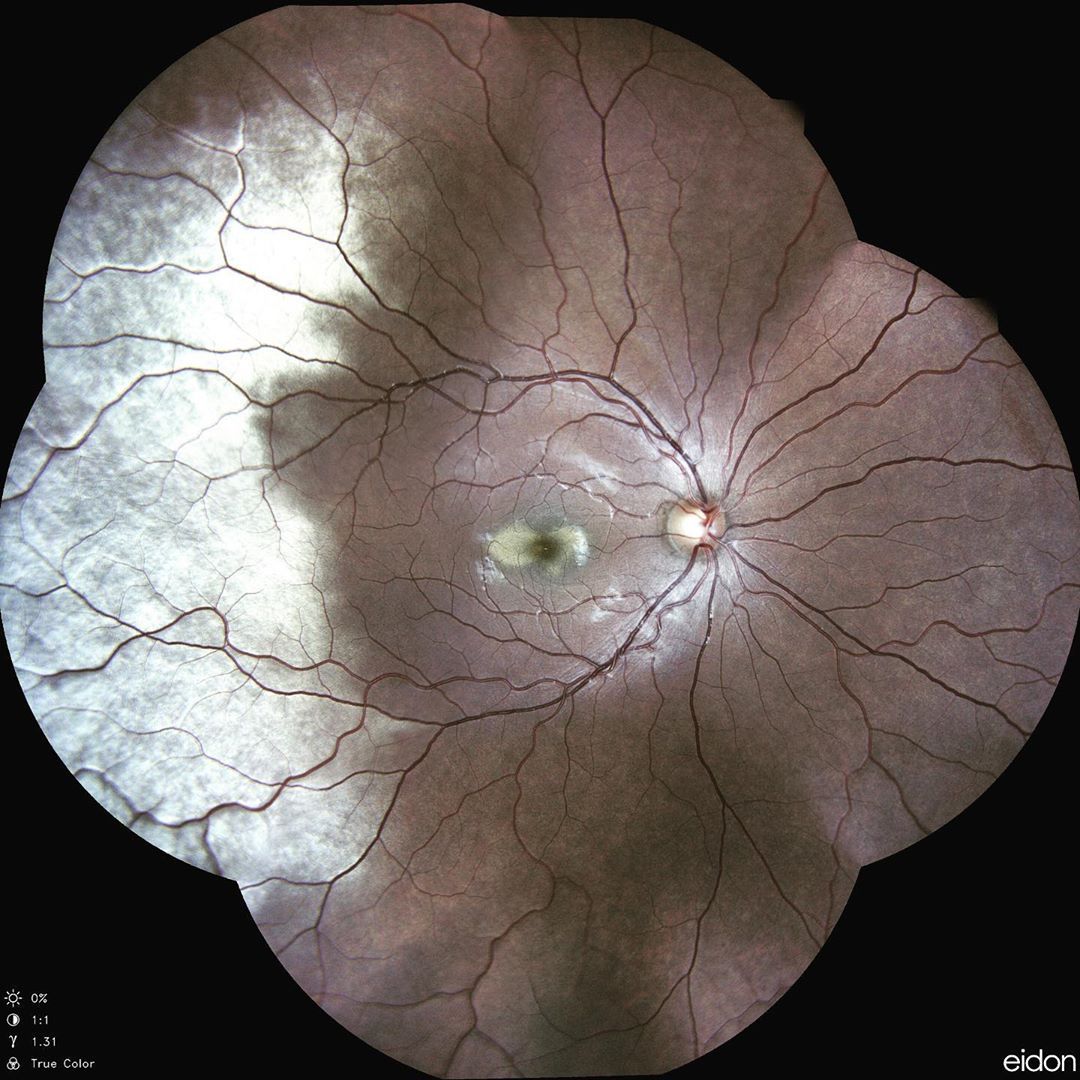

.@icare_usa released two new, next-generation imaging and tonometry devices: CenterVue DRSplus confocal fundus imaging system and

Icare ic200 handheld tonometer for portable measurement of IOP. buff.ly/2WwYbOi #optometry